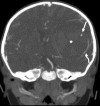

Gadolinium (Gd)-enhanced magnetic resonance imaging plays an essential role in the detection, characterization, and staging of intracranial neoplasms and vascular abnormalities. Although Gd is helpful in a majority of situations, it can lead to diagnostic misinterpretation in the setting of active vascular extravasation. Scarce reports of intracranial extravasation of Gd are present in the literature. Here, we report the first case of surgically proven spontaneous intraparenchymal extravasation of Gd mimicking an enhancing intra-axial neoplasm in a pediatric patient. Early and accurate recognition of Gd extravasation is critical in obtaining the accurate diagnosis and triaging patients expeditiously into proper avenues of care.